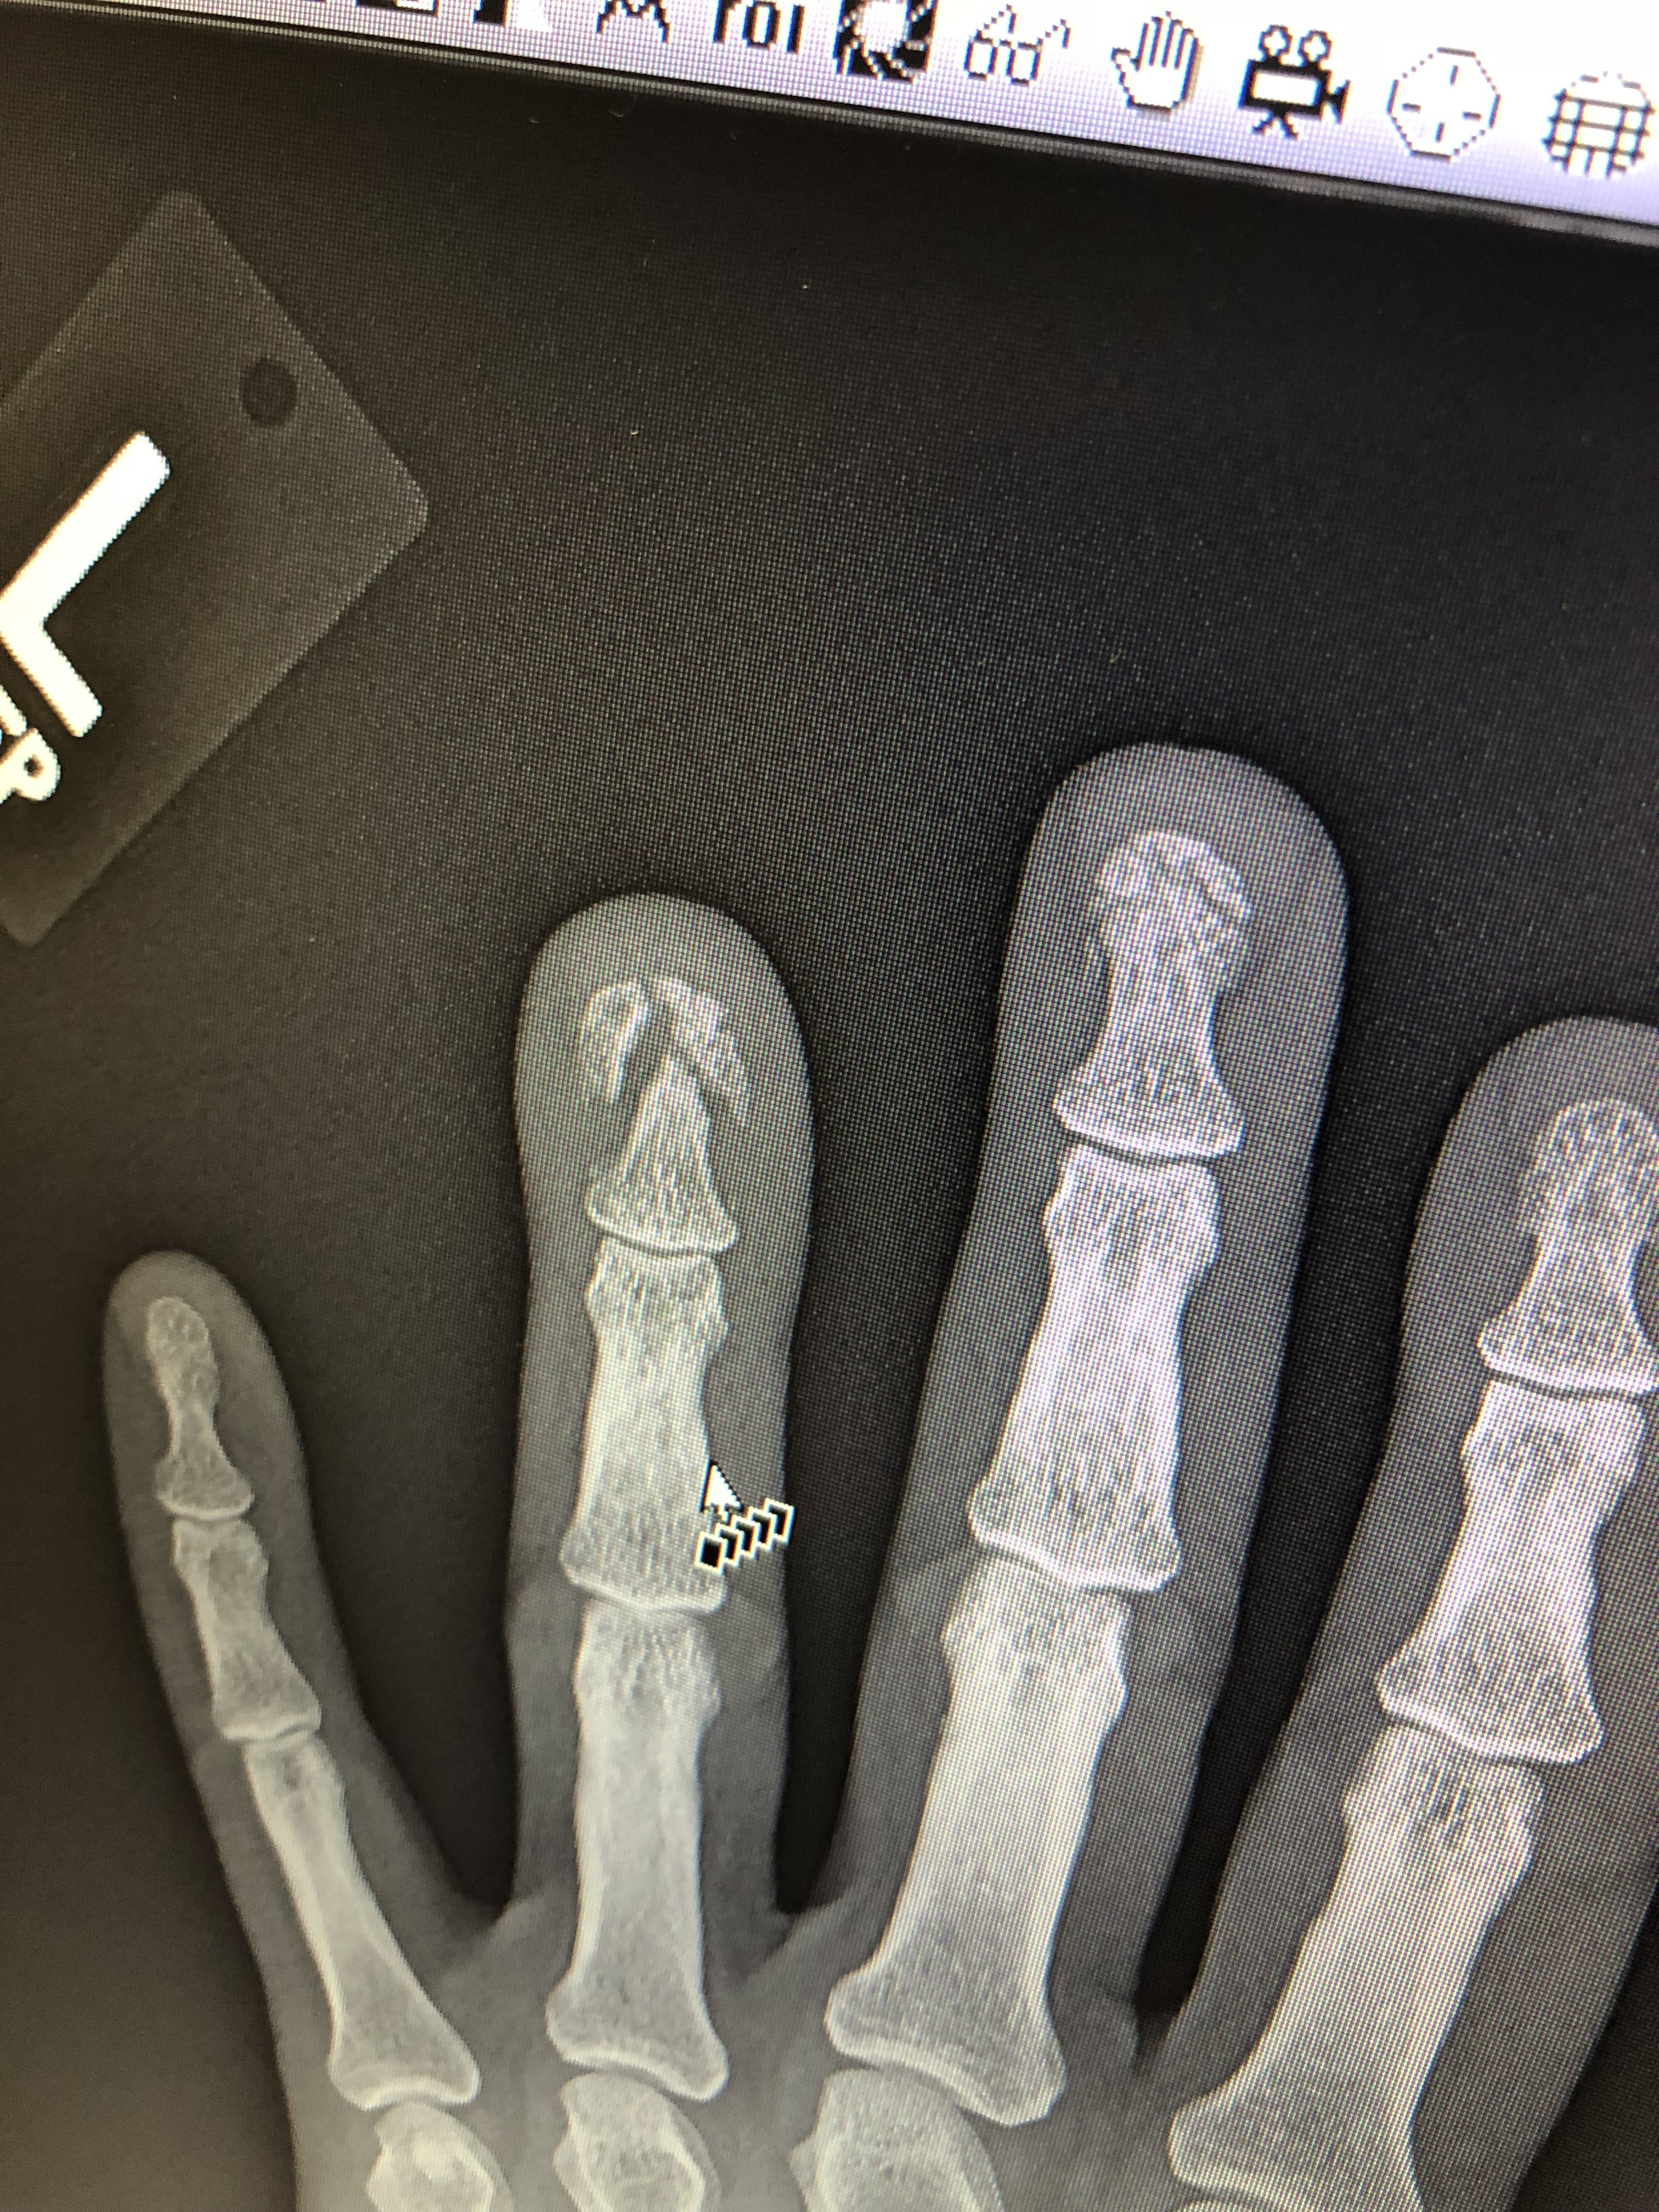

·Let’s just say a someone you know broke some fingers at an old job that required a couple surgeries. Fortunately this person only lost about 10% use of a couple fingers. Anyway workman’s Comp offered this person some money to shut up. The issue is a little more complex as this person may require another surgery but that part has been worked out. So anyway if this poor slob I’m talking about really wanted an smp. It’s kinda his grail and if this guy used some of that money to purchase an smp without telling his significant other would you consider this guy to be unethical and not cool? The guy isn’t a bum or anything he works and does other stuff, can’t do what he used to do because of the hand issue but worked things out despite himself. I am just asking for a friend as he said something about the devil and an angel whispering in his ear at the same time, not sure what he meant of course.